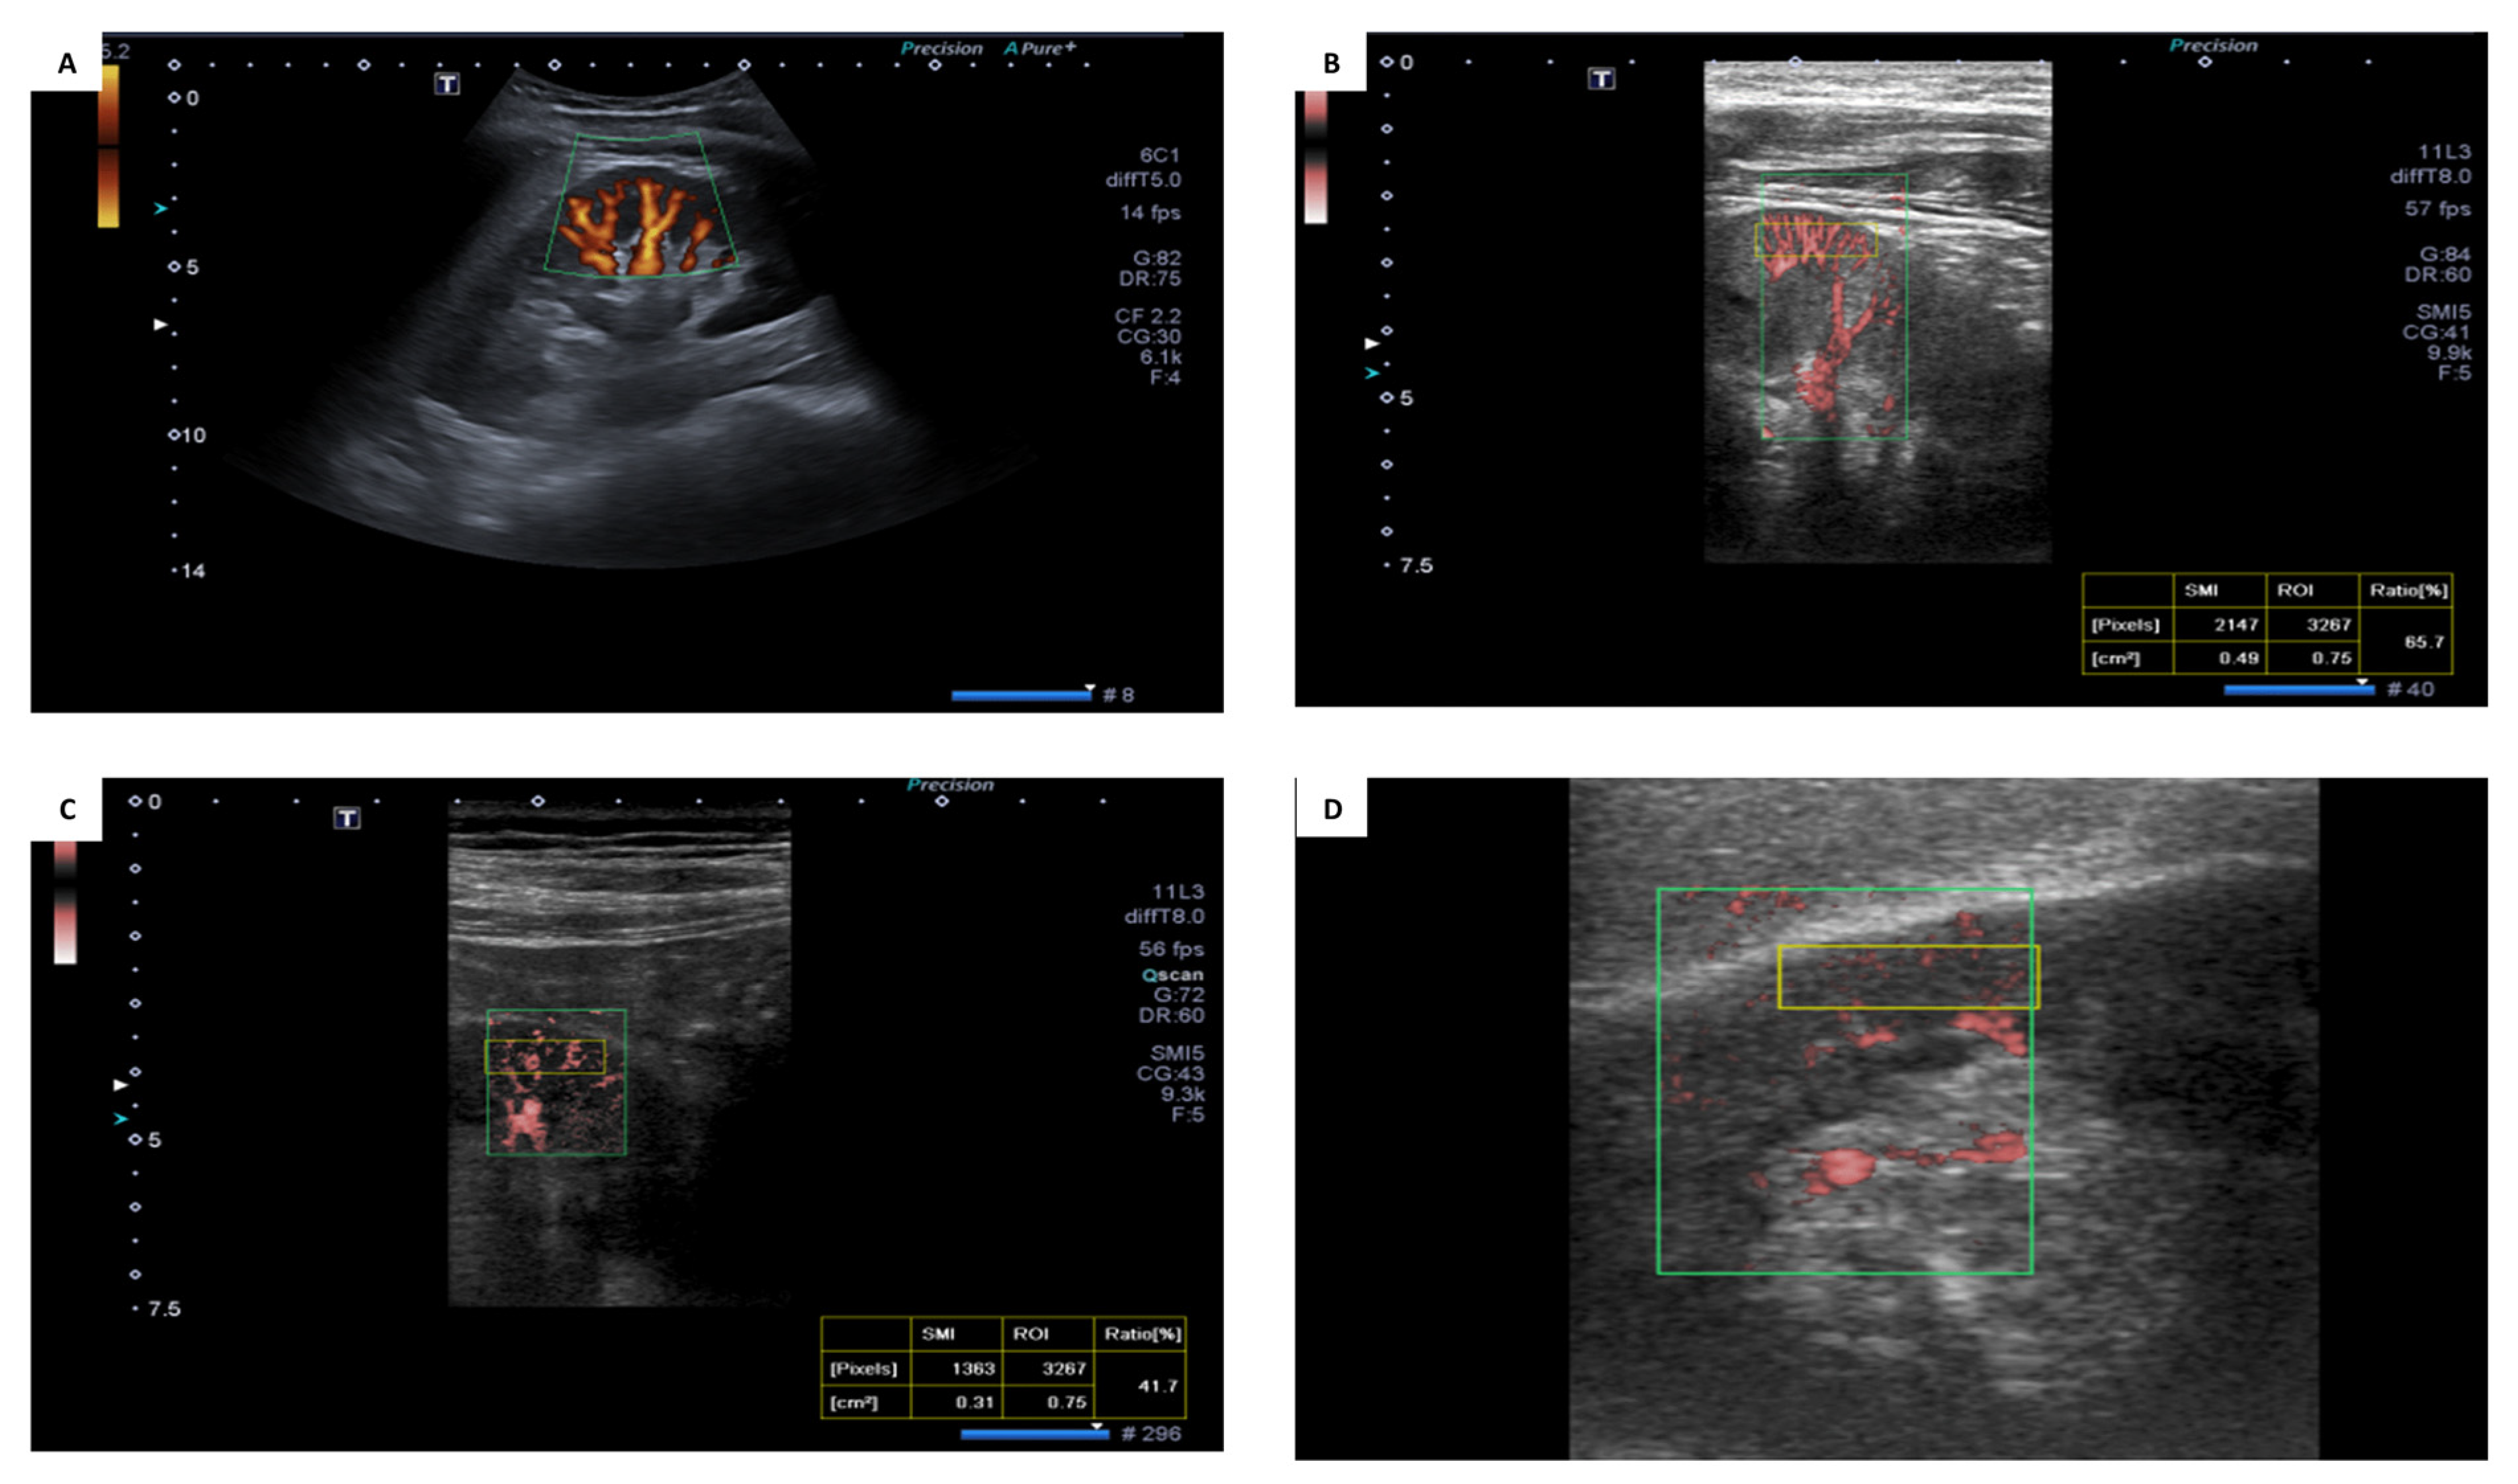

2.2. Superb Microvascular Ultrasound Imaging